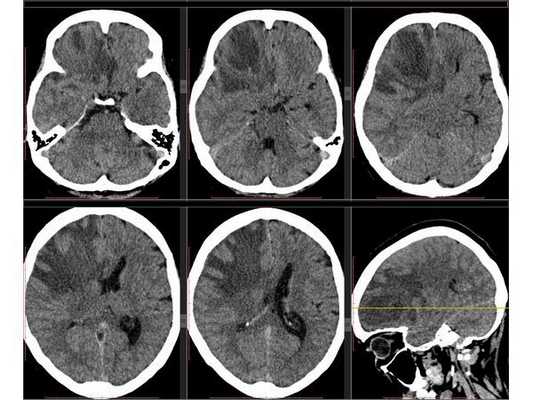

Рентгенография лёгких: без патологии. УЗИ органов брюшной полости: выявлены хронический холецистит, хронический панкреатит, диффузные изменения печени и поджелудочной железы. ЭКГ: в норме. На КТ головного мозга визуализировалось объёмное образование в правой лобной доли. Это вызвало подозрение на абсцесс, но отсутствие уровня жидкости, лихорадки и менингеального синдрома у пациентки в большей степени склонило клиническую мысль в сторону онкологического поражения. В связи с этим пациентку госпитализировали в отделении неврологии. Однако при осмотре онкологом и гинекологом данных, которые бы подтверждали наличие онкологии головного мозга, обнаружено не было. В качестве дообследования проведена КТ головного мозга с контрастным усилением. Она выявила объёмное образование в правой лобной доли с чётко очерченной капсулой. Рядом с образованием располагался отёк, срединные структуры были смещены влево примерно на 5 мм.

3D-реконструкция объёмного образования правой лобной доли головного мозга, выполненная на основании сканов КТ с контрастным усилением

Инкапсулированный абсцесс мозга на КТ имеет вид округлого объемного образования с четкими ровными контурами повышенной плотности (фиброзная капсула). В центре капсулы зона пониженной плотности (гной), по периферии видна зона отека. Введенное контрастное вещество накапливается в виде кольца (по контуру фиброзной капсулы) с небольшой прилежащей зоной глиоза.